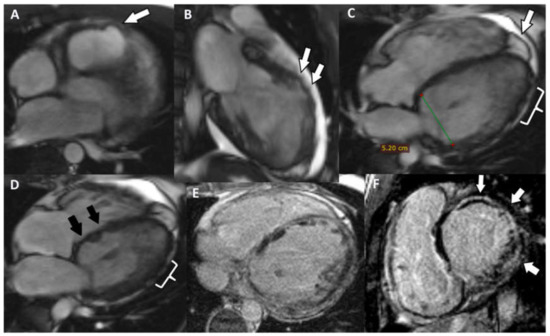

5. Cases Presentation